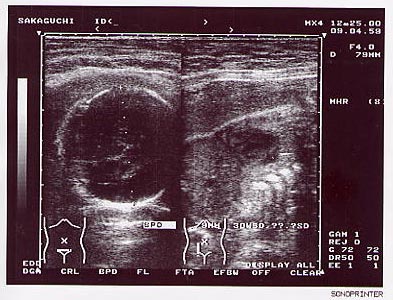

◆写真◆

ベイビーのエコー写真です